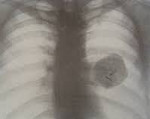

Часто доброкачественные опухоли легких являются случайными рентгенологическими находками, обнаруживаемыми при флюорографии. При рентгенографии легких доброкачественные опухоли легких определяются как округлые тени с четкими контурами различной величины. Их структура чаще однородная, иногда, однако, с плотными включениями: глыбчатыми обызвествлениями (гамартомы, туберкуломы), костными фрагментами (тератомы).

Детально оценить структуру доброкачественных опухолей легких позволяет компьютерная томография (КТ легких), определяющая не только плотные включения, но и наличие жировой ткани, свойственной липомам, жидкость - в опухолях сосудистого происхождения, дермоидных кистах. Метод компьютерной томографии с контрастным болюсным усилением позволяет дифференцировать доброкачественные опухоли легких с туберкуломами, периферическим раком, метастазами.